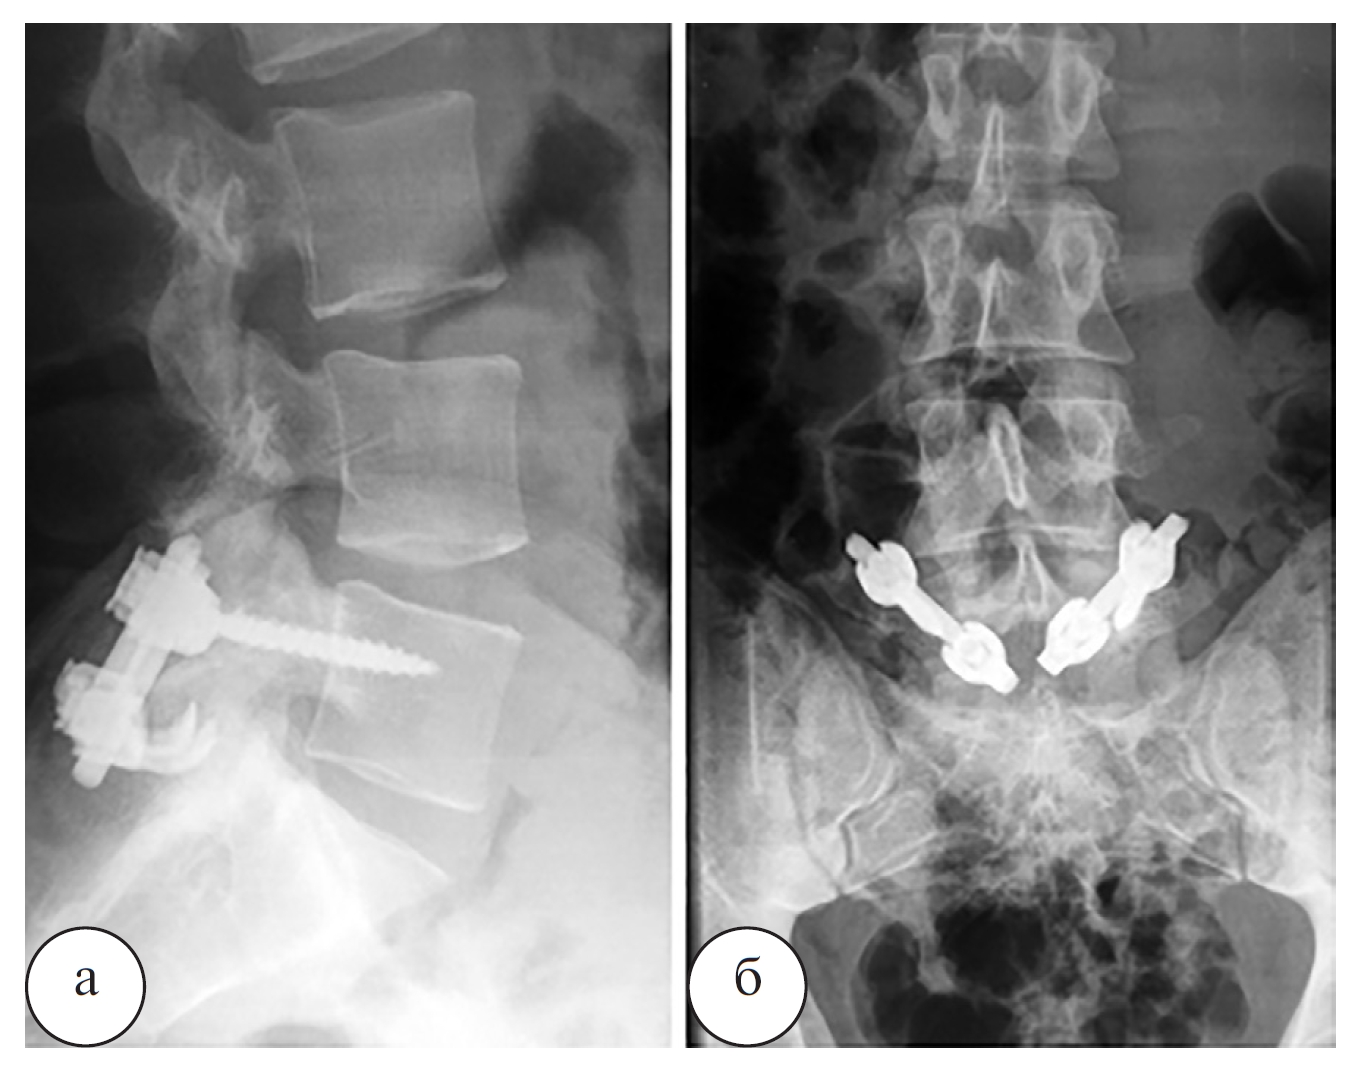

Рис. 3. Рентгенограммы пояснично-крестцового отдела позвоночника пациента О. после операции: а – боковая проекция; б – переднезадняя проекция

Наблюдение 1. Пациент О., 19 лет, профессиональный спортсмен. Диагноз: двухсторонний спондилолиз L5 позвонка с болевым синдромом. Рентгенограммы, МРТ и КТ пациента О. до операции, сразу после операции и через 4 месяца после операции представлены на рисунках 2–4.

Ранних и поздних осложнений после операций не было. Во всех случаях достигнута стабильная компрессия и фиксация спондилолизного дефекта с двух сторон. У двух пациентов со спондилолистезом I степени по данным контрольной спондилографии была отмечена частичная или полная редукция смещенного позвонка (табл.). Длительность операции при одноуровневом спондилолизе составила в среднем 154±25 мин, кровопотеря – 100–150 мл. В целом результаты лечения больных прослежены в сроки от 1 года до 8 лет после операции. Отчетливые признаки перестройки костных трансплантатов в зоне спондилолизных дефектов были выявлены при контрольной КТ через 4–6 месяцев после операции. Полное сращение спондилолизных дефектов в зоне костной пластики было отмечено через 8–12 месяцев. Все пациенты отметили купирование болевого вертеброгенного синдрома в течение первого месяца после операции. Во всех наблюдениях прогрессирования спондилолистеза отмечено не было. После периода реабилитации все пациенты вернулись к прежнему уровню физической активности, а через 12 мес. после операции средние значения индекса ODI снизились до уровня минимальных нарушений. В течение периода наблюдения прогрессирования дегенеративного процесса в смежных межпозвонковых дисках не отмечено.